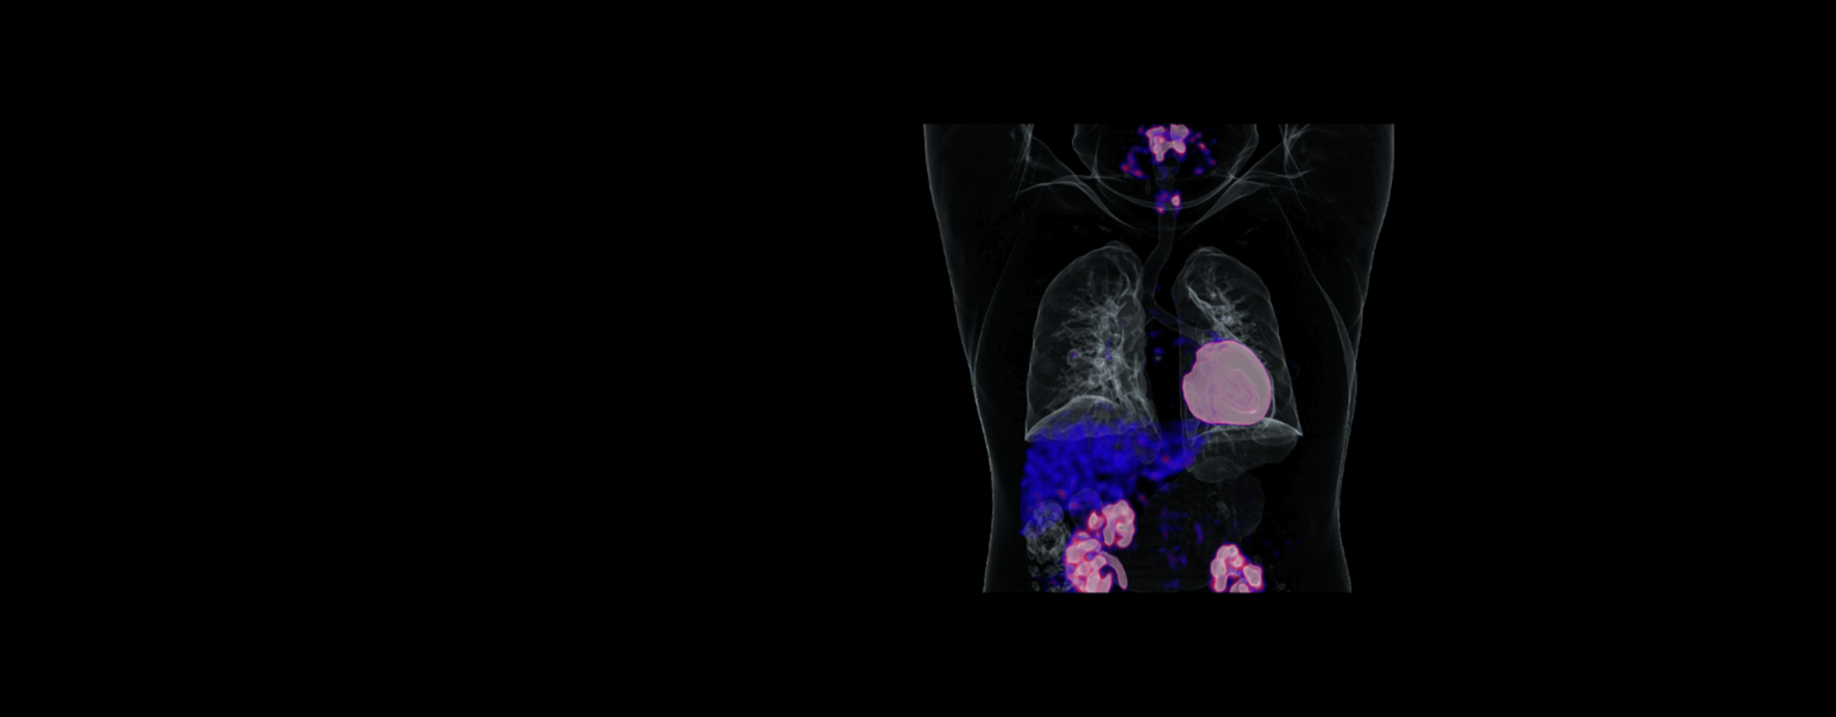

MI图像融合

支持融合查看多种医学影像数据,拥有便捷的阅片工作流,灵活的用户配置以及常用的图像处理工具。